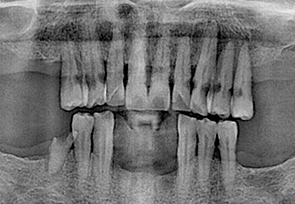

• before

• after